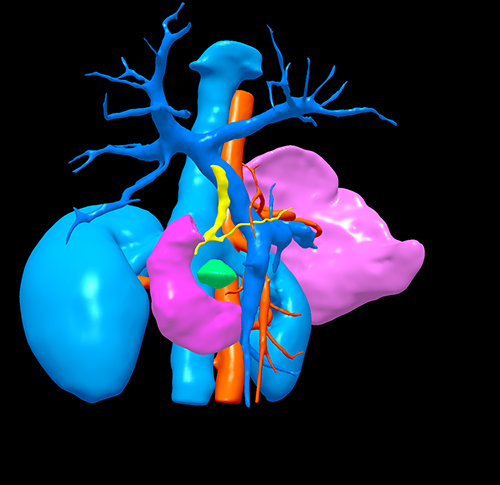

肿块型慢性胰腺炎----胰十二指肠切除